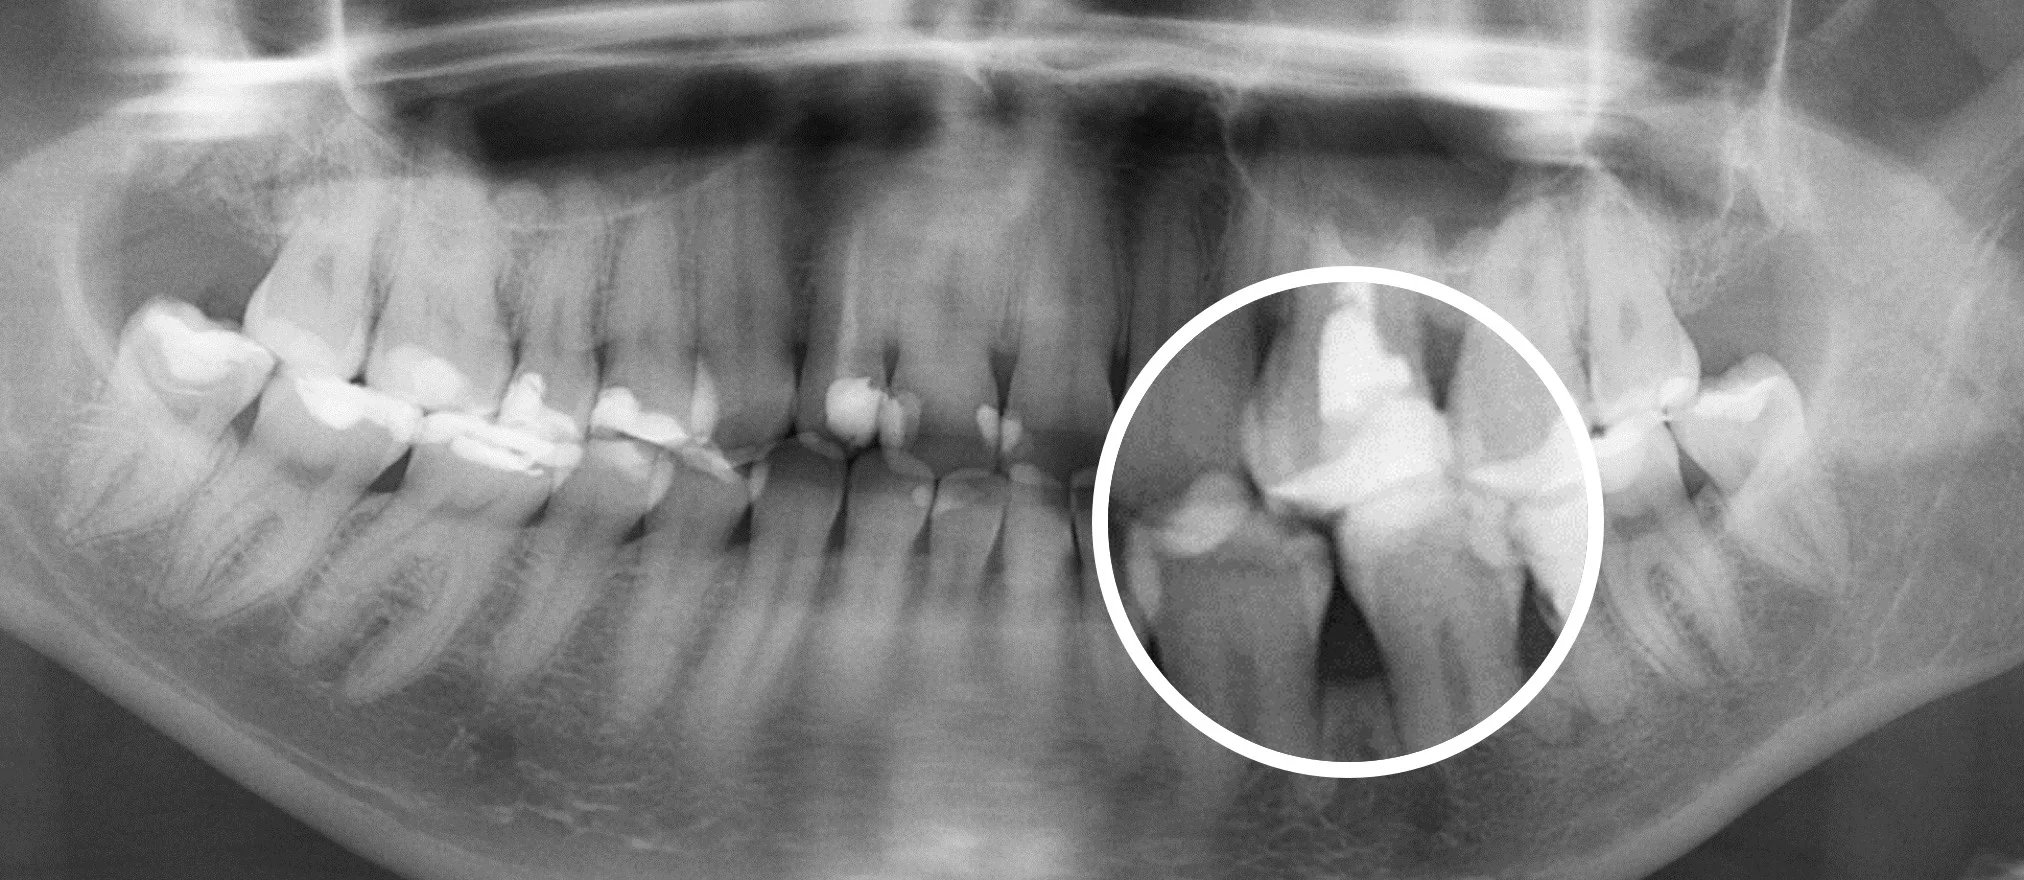

Еще 10 лет назад для того, чтобы провести диагностику зубов стоматологи использовали прицельные R-снимки и ОПГ снимки. Это снимки, которые делаются в 2D формате. Единственное, что врач мог делать с данным снимком, это приближать и удалять изображение.

Сравнение 2D и 3D снимков

3D снимки — это новый уровень диагностики. Но при их появлении возникла достаточно большая сложность.

Дело в том, что 3D снимки гораздо более информативны, чем 2D снимки, но на их чтение требуется гораздо больше времени и более высокая квалификация стоматолога, это гораздо более трудоемкий процесс.

Далеко не каждый стоматолог, умеет правильно читать КТ снимки, для этого требуется отдельное обучение. Также стоматологам не хватало времени выделяемого на прием, чтобы проанализировать каждый зуб.

Что привело к тому, что комплексность диагностики начала страдать. Врачи успевали проанализировать только 1-2 зуба за прием.